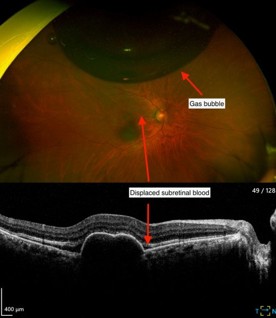

The following day, VA had improved to 6/24, and IOP was normal. Fig 2 shows inferior displacement of the submacular haemorrhage away from the fovea. The patient was instructed to continue face-down posturing for another two days. The patient subsequently continued monthly intravitreal bevacizumab injections, then moved to a treat-and-extend regimen.

Fig 2. Presence of gas bubble and

displaced subretinal blood